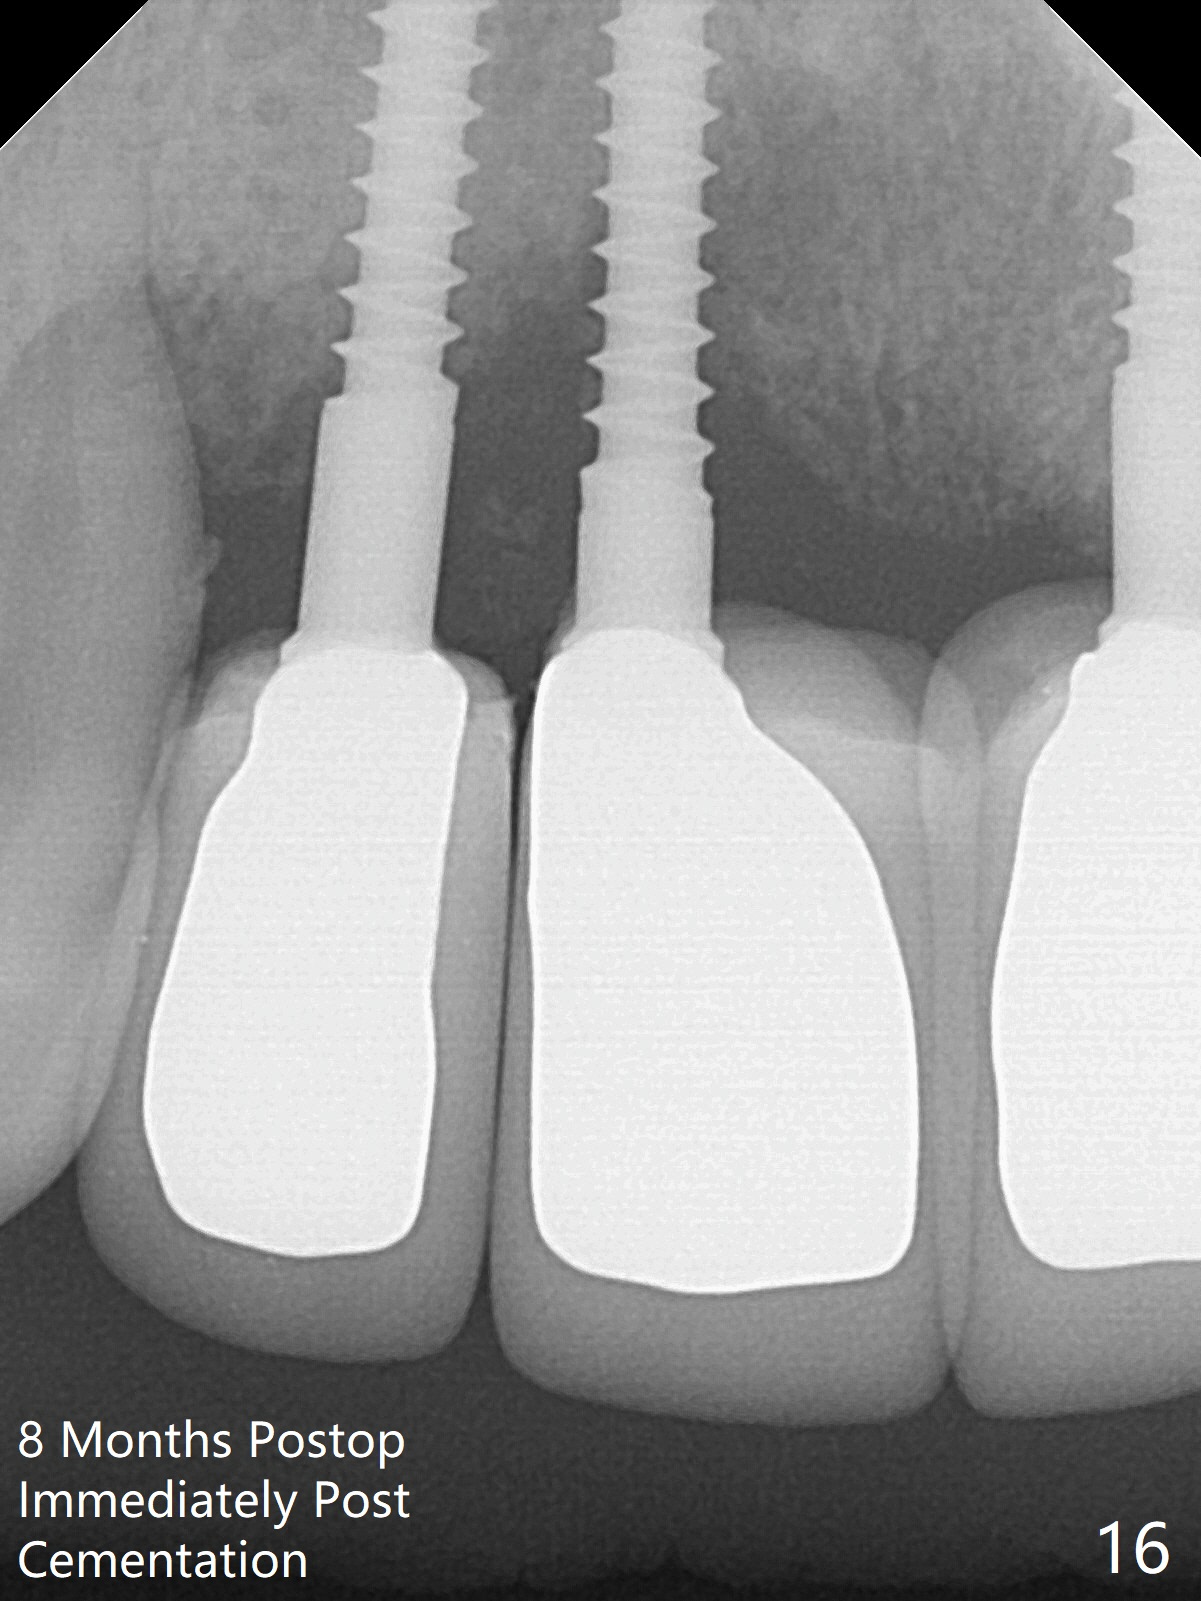

Although the ridge of the maxillary anterior ridge looks moderate in width (Fig.1), the bone is ~4 mm buccopalatally. Suction down surgical stent (Fig.2') made from the lab-fabricated provisional (Fig.2) will be used to check the position and trajectory of osteotomies. PAs taken after initial osteotomies (1.2 mm drill) show those at the central incisors tend to be mesial (close to the Incisive Canal *), while those at the lateral incisor sites distal (Fig.3,4). After adjustment, the position and trajectory of the osteotomies are acceptable (Fig.5,6). To reduce the chance of perforating the Incisive Canal (Fig.3,4 *), 2.5 mm 1-piece implants are inserted with >40 Ncm (Fig.7,8). After deep placement of the implants, Vanilla graft is placed at the crest (Fig.9,10 *). An immediate splinted provisional is fabricated from the suction down stent. The gingiva is healthy around the provisional (Fig.11) and the implants (Fig.12,13) 1 month postop. The provisional is adjusted monthly so that the interdental papillae can be elongated. No bone resorption is observed 6 months postop (Fig.14,15). Crowns are cemented 8 months postop (Fig.16-18). The keratinized gingiva appears to have formed the abutments 8 months postop immediately pre-cementation (Fig.19).